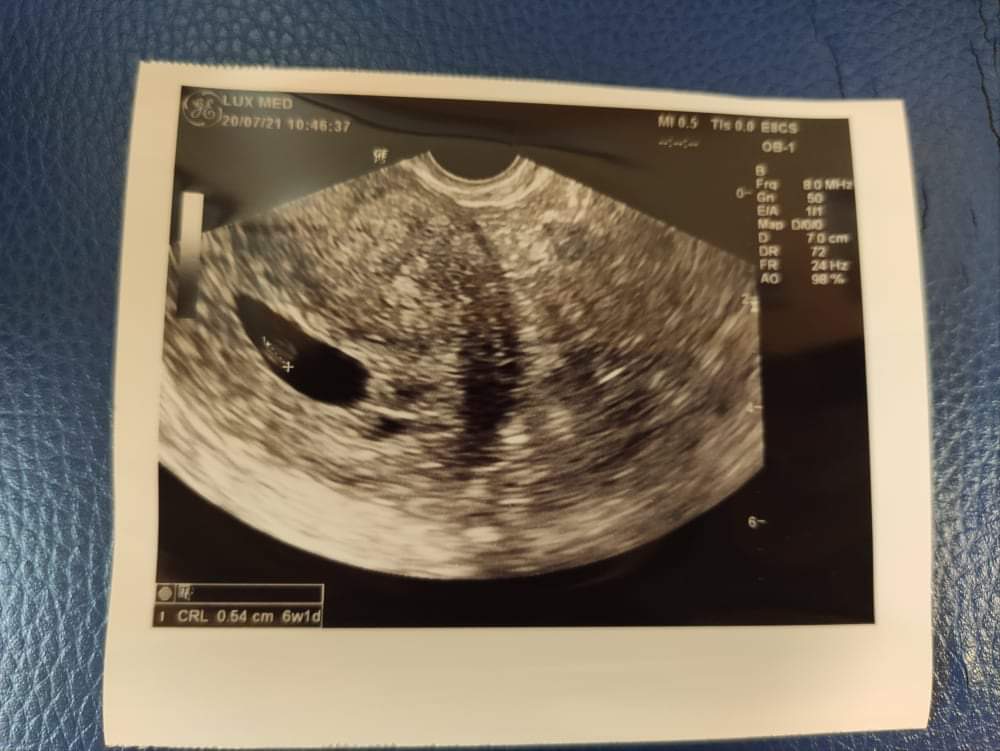

Witam kobietki , chciałam się poradzi Ci j tym myślicie. Test ciążowy pozytywny w poniedziałek tydzien temu , betaHCG we wtorek wskazywała na 5ty tydzien. Dziś byłam na usg i widoczny jest pęcherzyk ciążowy a w nim żółtkowy ale zarodka brak ... dziś z USG 6tyg+1dzien . Co o tym myśleć 1.5 roku starań bardzo się boję . Jutro jadr powtórzyć betę.

Mam tylko to , zbytnio się nie znam

• 1671476792110469156748722337696.jpg

1671476792110469156748722337696.jpg

1,1 MB · Wyświetleń: 186